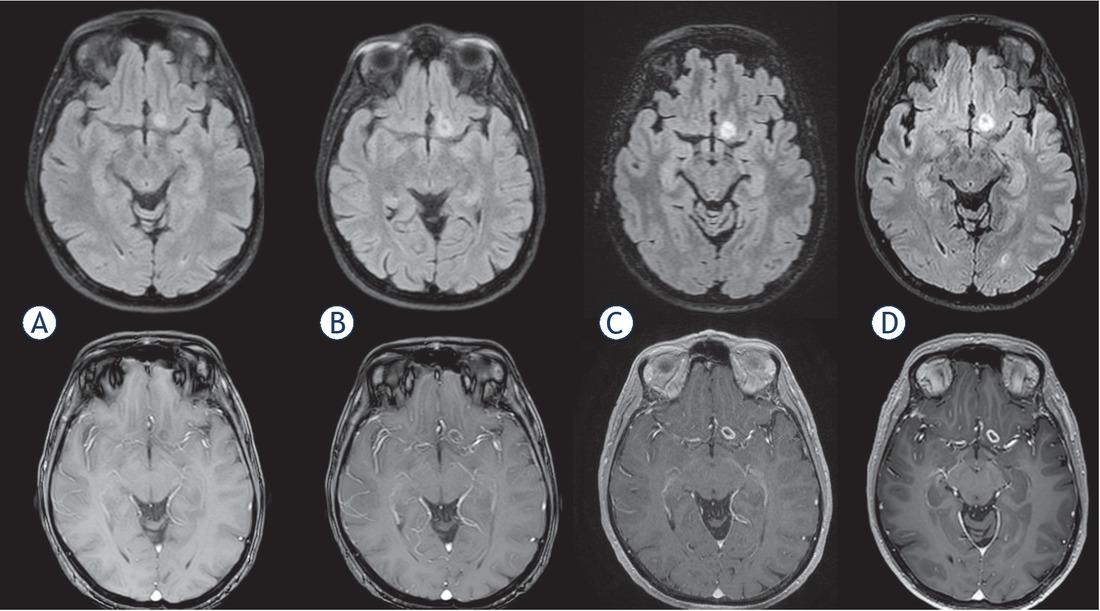

A 56 y.o. female patient underwent MRI for persisting headache. An incidental slight alteration of FLAIR signal in the left gyrus rectus was discovered. MTD was 7.37 mm. She repeated an MRI 5 months later to evaluate tumor evolution and an EN appeared in the previously FLAIR-altered area. MTD of the EN was 7.37 mm, whereas MTD of FLAIR-altered area was 12.6 mm and there were no further changes in the next MRIs. An MRI with spectroscopy was obtained one month later and this suggested a GBM. The new MTD of the EN was 8.43 mm. Surgical treatment was then proposed. She underwent preoperative MRI for neuronavigation one month later. MTD of the EN was 8.43 mm (Figure 3). Complete resection of EN was carried out and histopathological diagnosis revealed GBM IDH1 WT. She underwent adjuvant therapy with Stupp regimen and is still alive 12 months after surgery. All values of ΔMTD, VDE and Acc calculated according to equations [2], [4,] [5], [6], [7] for every MRI scan are listed in Table 1, divided for FLAIR and EN volumes.

MRI scans in Patient 4 at 0 (A), 160 (B), 196 (C) and 223 (D) days (fluid attenuated inversion recovery [FLAIR] and T1 with gadolinium sequences).